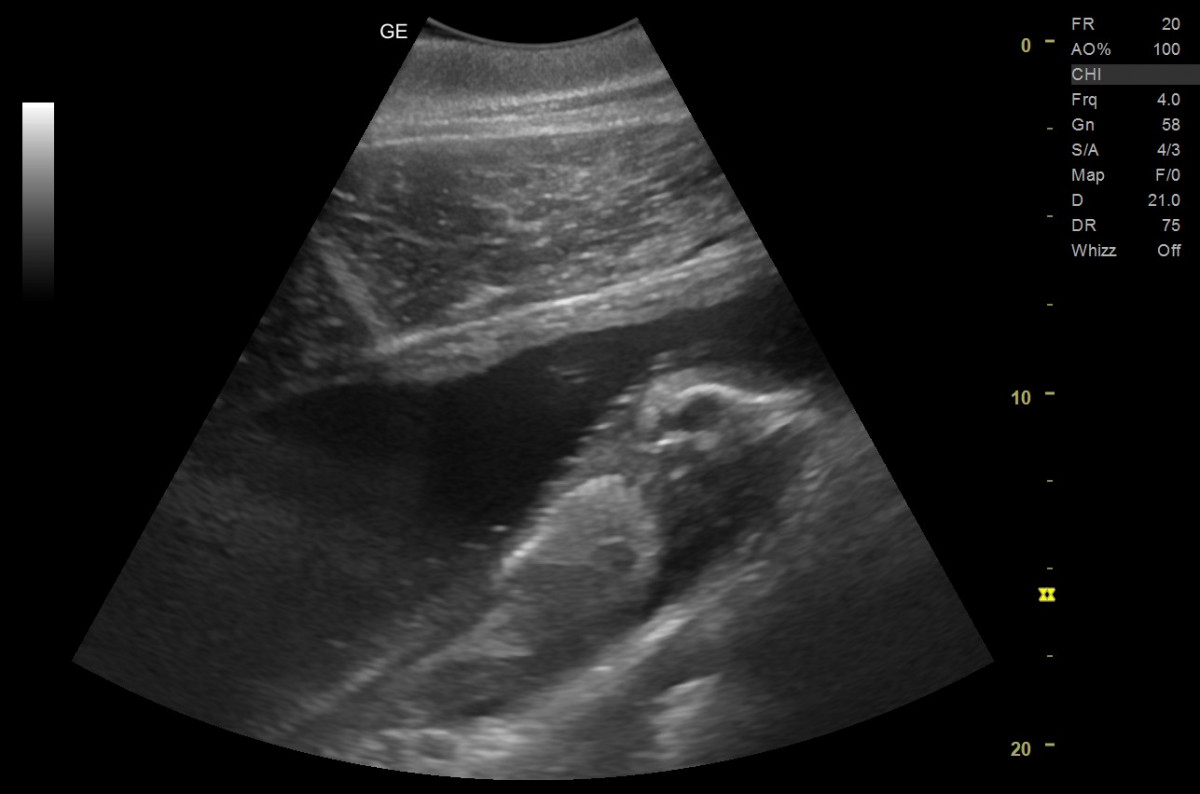

ハンドウイルカの「テン」=超音波検査により胎仔の動きを確認 (2/2枚)